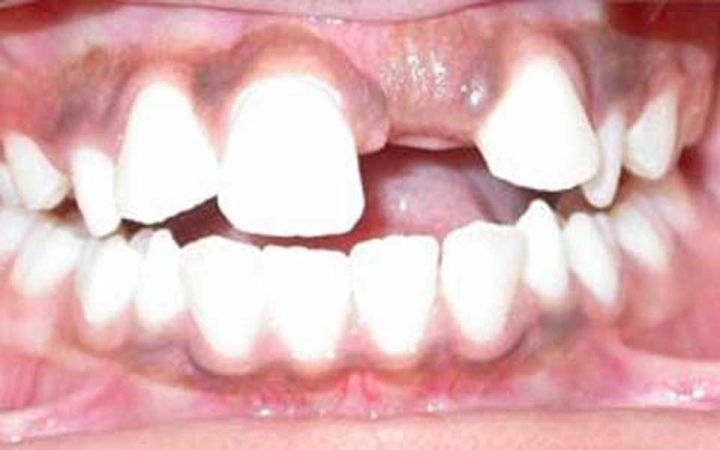

最为常见的是上颌切牙的迟萌。乳切牙因为外伤、蛀牙等原因,造成了过早脱落,致使牙龈反复摩擦增厚,导致下面的恒牙萌出困难,此时需要去进行牙齿助萌。

上颌切牙迟萌

(来源:http://www.identalhub.com/blog/930/delayed-eruption-of-teeth)